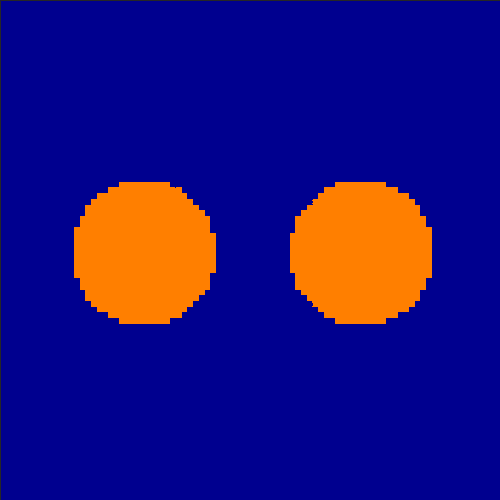

In order to test the behaviour of the proposed method in a more realistic, random-based test case, we performed a Monte Carlo simulation for dynamic SPECT imaging. First, we created a simple image phantom consisting of an outer and two inner circles which represents the structure of the region of interest (see figure 8(a)). Within those regions we assumed concentration curves over a time period of 90 time steps as displayed in figure 8(b). Based on the tracer intensity in an image frame at each time step, we created a variable number of random decay events (where the number is proportional to the average concentration in one pixel in the whole image frame per time step) with a probability proportional to the concentration in every subregion. They are detected by a virtual double head gamma camera rotating around the patient by 46 degrees per time step, which consists of 374 detector bins. Every simulated decay event is projected onto the scanner and counted by the corresponding detector bin.